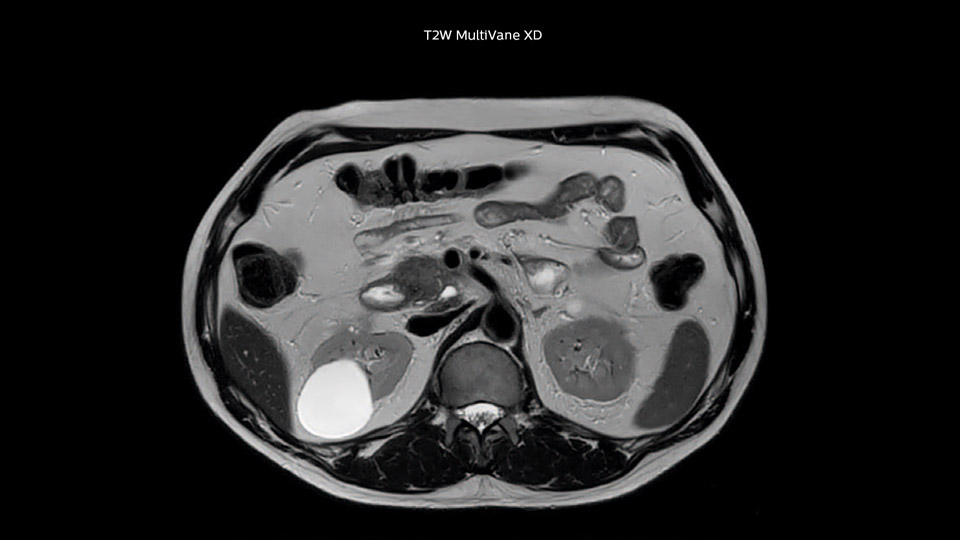

Comparison of liver MRI with and without MultiVane XD motion correction

In this example the image quality of the MultiVane XD images is evidently better than in the images without MultiVane XD. Ingenia 1.5T with dS Torso coil solution.

“We acquire one transversal high resolution T2-weighted sequence with 3 mm slice thickness, for example for pancreas or liver lesions. Then we also add a T2 fat suppressed MultiVane XD SPIR sequence. We perform these two routinely in our liver imaging. We use high dS SENSE factors to significantly shorten scan times to 2-4 minutes, which can improve our protocol; it’s a very robust scan.”

“I would absolutely recommend to other sites to implement MultiVane XD with dS SENSE in their abdominal cases, as it’s brilliant for robust, motion-corrected abdominal imaging. It provides us with excellent image quality with high resolution in a short time,” says Dr. Baumann. “I would advise using MultiVane XD for T2 and T2 fat suppressed high quality imaging for almost every liver case.”